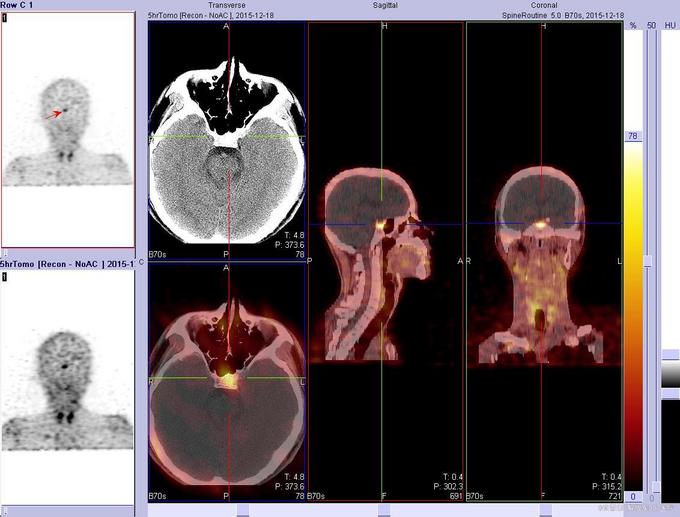

查体:神志清楚,不能独立行走,消瘦体型,胸廓、腰骶部、颈椎等多处骨骼有明显压痛。心肺腹未见明显阳性体征。 辅助检查:PTH:86.61(15-65pg/ml);25-D3:5.8(20-32);ALP:264.8(0-130u/l);血P:0.34(0.89-1.6mmol/l);血Ca:2.2(2.09-2.54mmol/l);骨密度:严重骨质疏松;X线:可见病理性骨折。奥曲肽显像:垂体瘤不除外。颈部CT:左侧甲状旁腺不除外结节样改变。